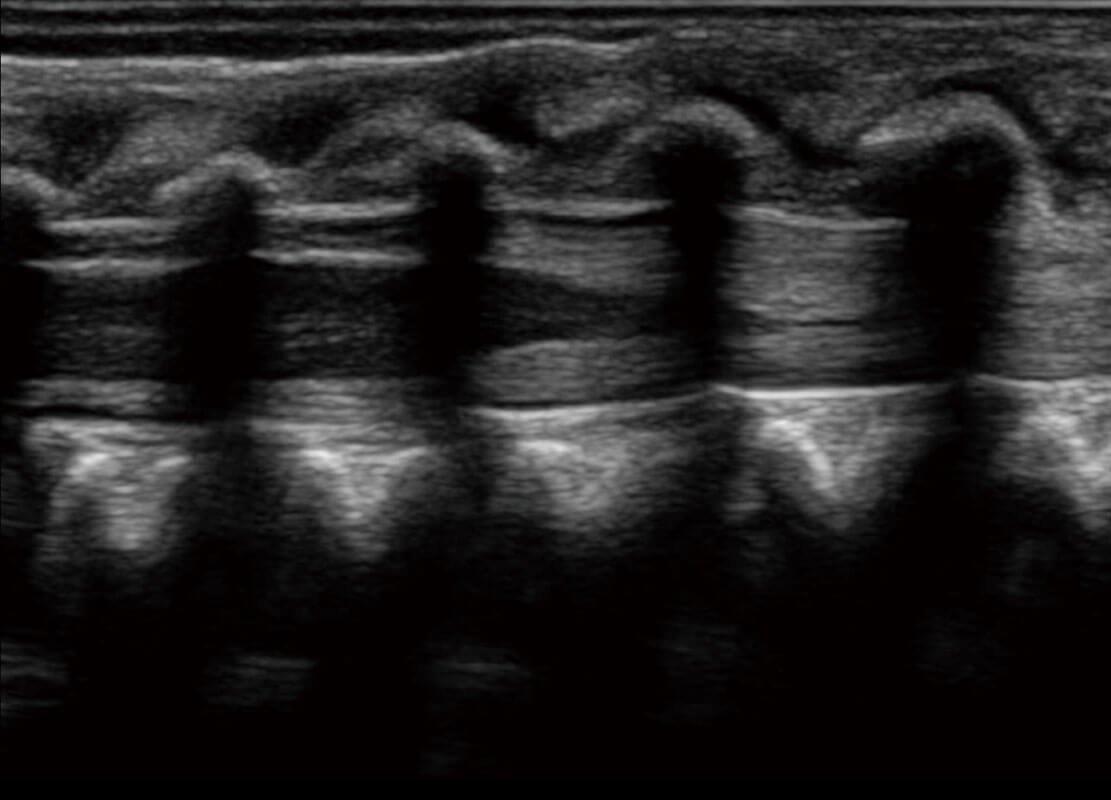

新生儿脊髓圆锥

新生儿心脏

P60搭载宽频带线阵探头、宽景成像、弹性成像技术,为您提供乳腺应用方案。P60支持高频相控阵探头、线阵探头、腹部高频探头、腹部微凸探头等,丰富的探头群搭载敏感的彩色血流成像,适用于新生儿多种脏器检测要求,满足新生儿筛查需求。